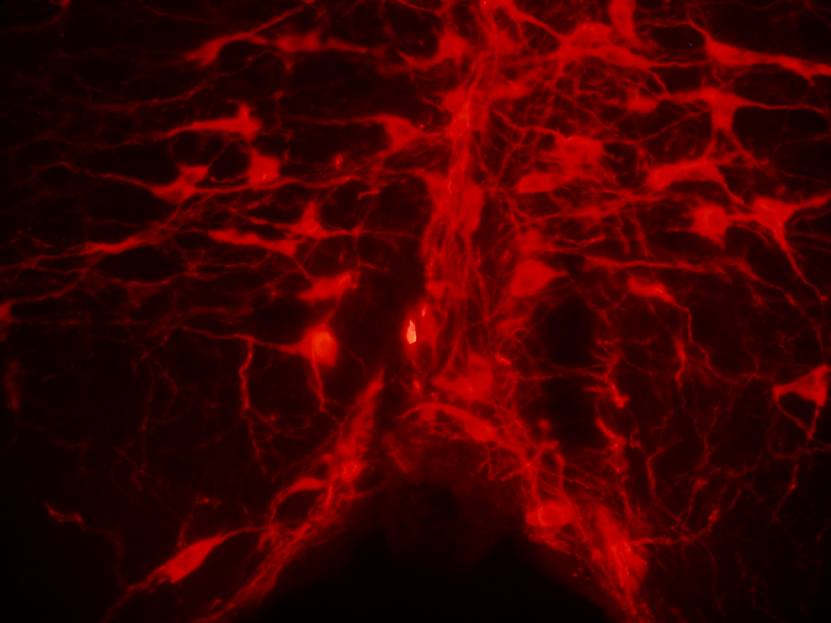

(b) Red image example

Figure 2: Data preview. The figures show examples of fluorescence micrscopy pictures (Figures 2(a), 2(b) and 2(c)) and the corresponding ground-truth binary masks (Figures 2(d), 2(e) and 2(f)).

The red collection comprises images obtained from multiple unpublished experiments, concerning specimens of both mice and rats (cf. Figure 2(b)). Despite sharing the same experimental setup as green and yellow collections, this time the brain tissues were stained for various elements to phenotypically characterize the cells involved in the neural circuits underlying the physiological phenomena of torpor and thermoregulation. Specifically, slices were stained for orexin, tryptophan hydroxylase, and tyrosine hydroxylase. In this case, image acquisition was conducted using both the aforementioned Nikon Eclipse 80i microscope and an ausJENA JENAVAL microscope, equipped with a Nikon Coolpix E4500 color camera, at a magnification of 250x. For further details, please refer to the accompanying metadata for each image.

Peculiar traits

In all image collections, the visual representation is characterized by the prevalence of two distinct color tones, which result from the deliberate selection of a specific wavelength. One tone appears darker, indicating areas where light has been filtered out, while the other tone is brighter and more intense, emitted by the fluorophore corresponding to the color of each collection (see Figures 2(a), 2(b) and 2(c)). As a result, the images can generally be depicted using variations of a single color. Consequently, a 1-D representation may be sufficient, or an alternative color space other than RGB could provide more informative and less redundant data.